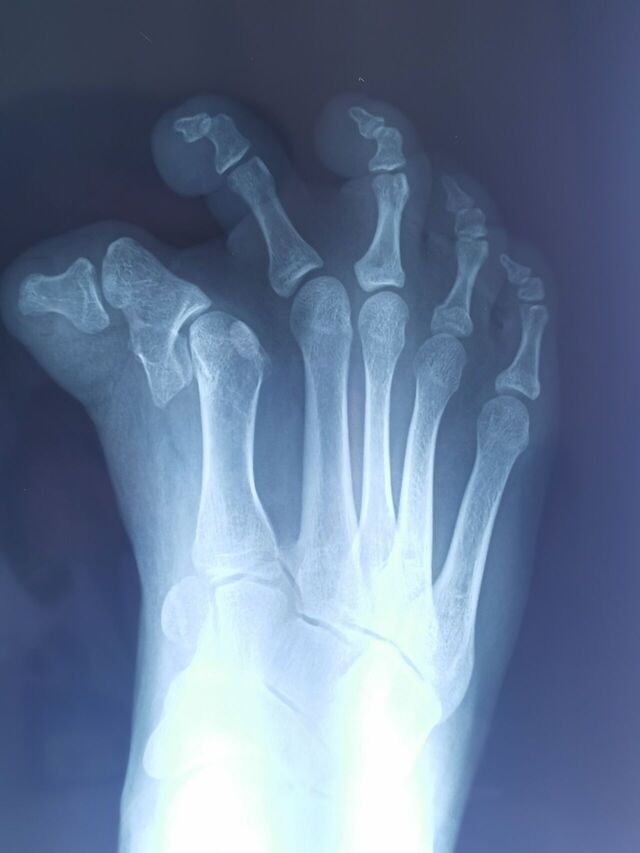

手术设计

另一例足拇趾多趾畸形术后